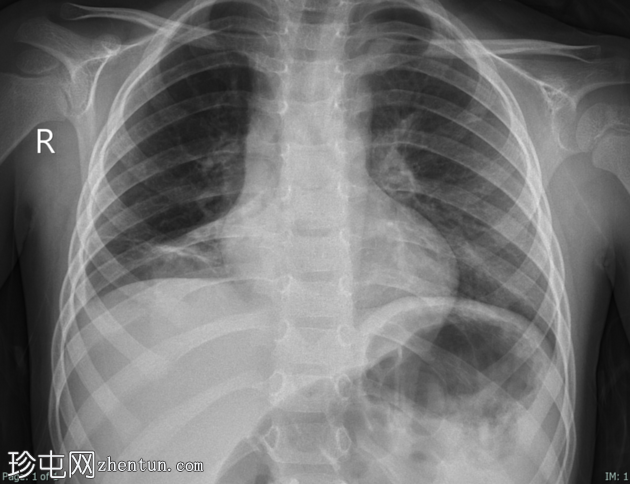

X线片

1.png

正位片

2.png

侧位片

底部可见边界不清的阴影,最符合呼吸道感染的表现。

正位和侧位片上偶然发现胸骨后肠管。